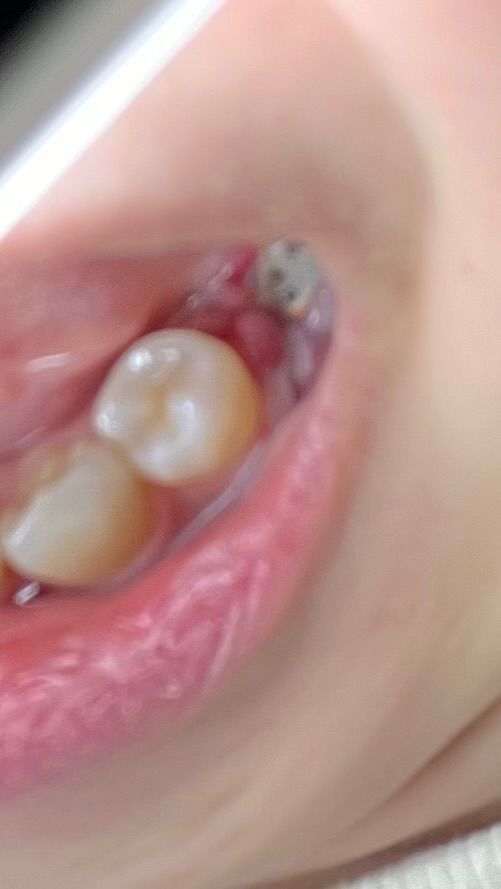

임플란트 3일차인데 뽈록하게 올라왔습니다 잘 아물고 있는걸까요?ㅠㅠ

다른부분은 하얗게 되어서 안심인데 요 부분이 아프면서 부풀었어요...

어제부터 이렇게 됐어요.

제가 항

생제 알러지가 심해서 2일만 약을 먹고 중단 했는데 하루만에 이렇게 됐습니다 ㅠㅠ

항생제 모든 종류가 다 알러지가 있어서 바꾸지 못하고 중단했거든요... 하루만에 염증이 생긴걸까요?? 불안하네요 ㅠㅠ

• 1번 째 사진

잇몸을 절개를한 부위에 음식물이 껴잇거나 염증이 생겻을 가능성도 잇으니 치과에 가셔서 소독을 한번더 받으시는게 좋을것같습니다.

임플란트 하고 나서 잇몸 부위에 자극이 되었거나 했으면 사진처럼 잇몸이 부어오르는 경우가 있습니다.

대부분 시간이 지나면서 저절로 안 물기 때문에 너무 걱정하지 않으셔도 됩니다 흡연을 하고 있다면이 몸에 치유가 느려질 수 있기 때문에 잇몸이 아물 때까지 금연을 하시는 것이 좋습니다.